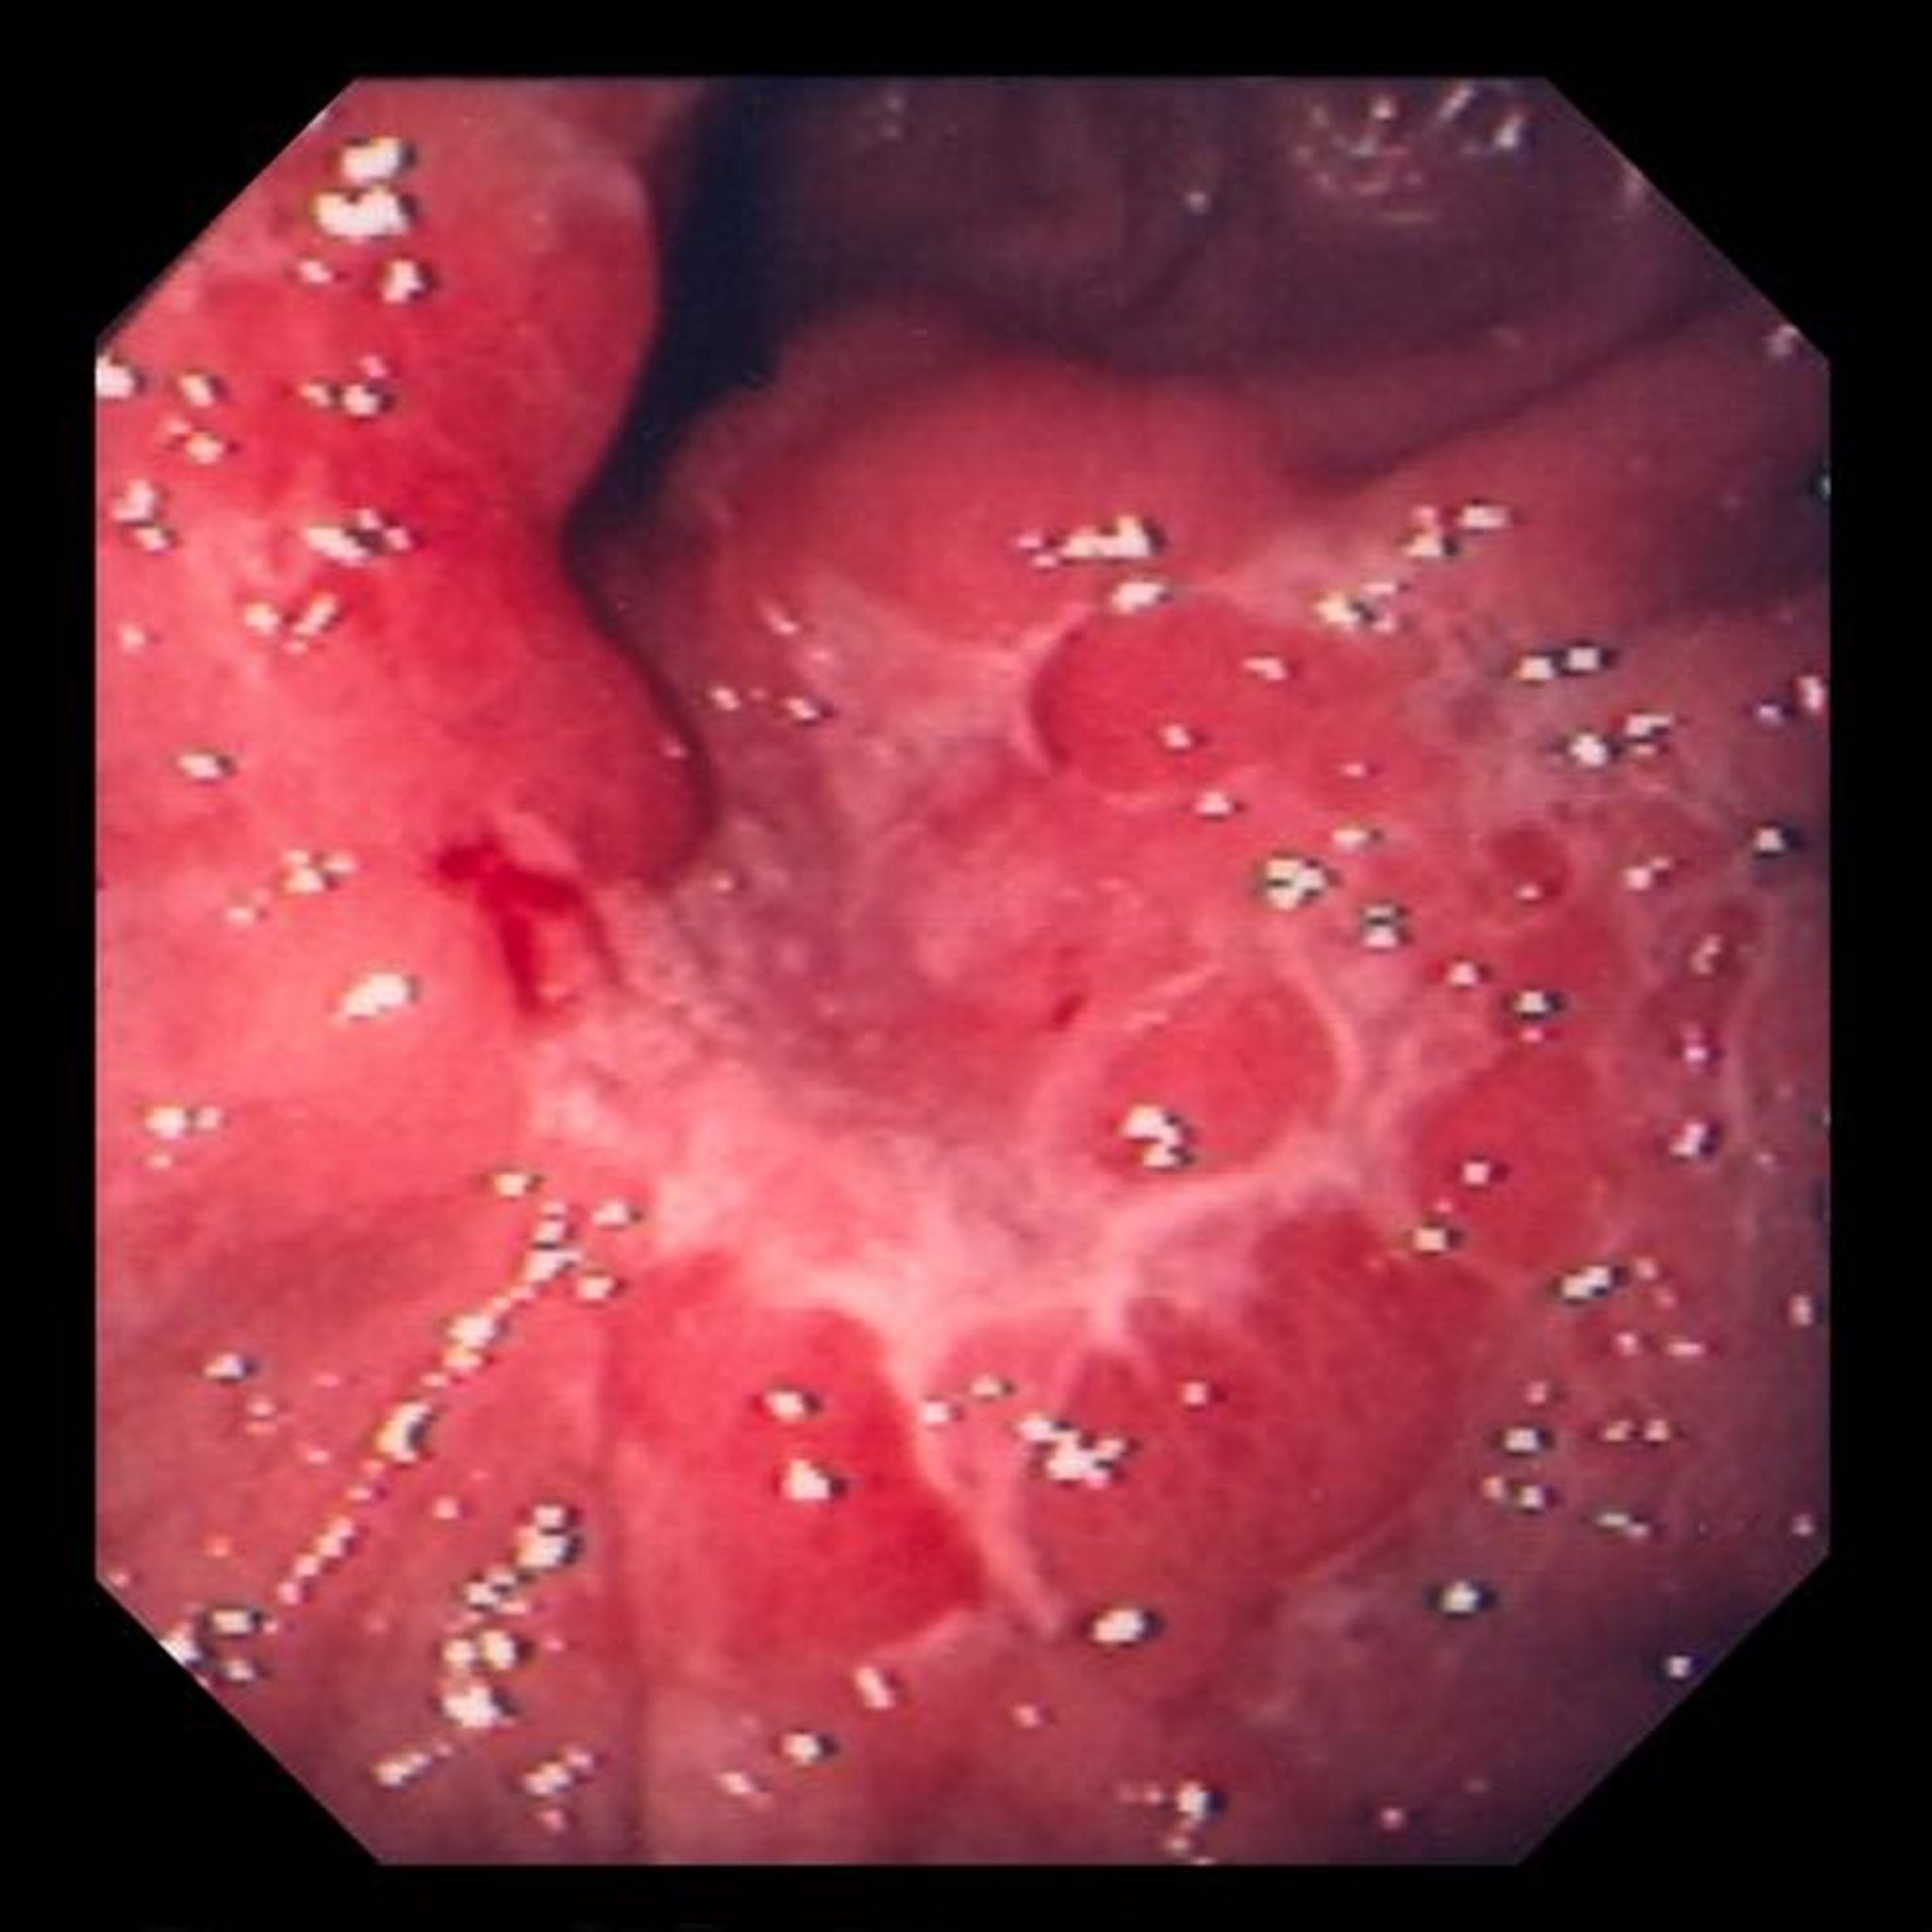

Questa immagine mostra un'ulcera all'interno delle pieghe mucose edematose, che, alla biopsia, si è rivelata essere un adenocarcinoma scarsamente differenziato (tipo cellulare ad anello con sigillo).

Image provided by David M. Martin, MD.